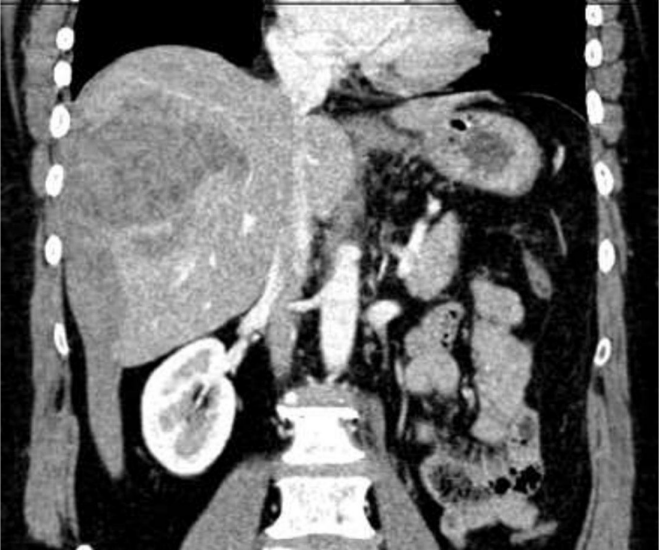

ACDC, 38 anos, sexo feminino, dá entrada no serviço de urgência, com quadro de dor abdominal em hipocôndrio direito que irradia para as costas, de forte intensidade, sudorese e taquicardia. Foi solicitada uma ultrassonografia, e, durante o exame, o radiologista optou por complementar com uma tomografia com contraste, com o seguinte achado:

Qual a principal hipótese diagnóstica para o quadro em questão?